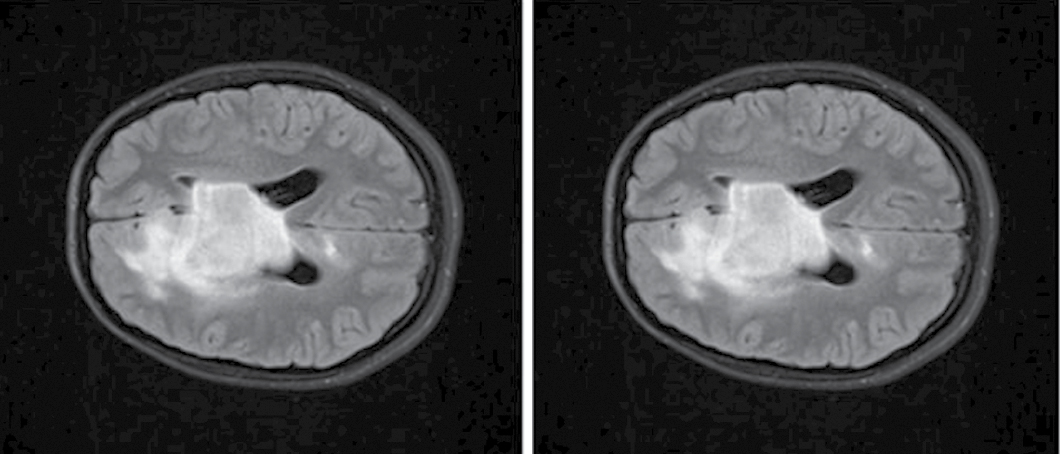

At the previous study stage, we found that the majority of the radiomic predictors characterize ROI heterogeneity by gray level intensity of the voxels. Hence, the higher performance of the model built using the method of the current study stage can be associated with the contrast adjustment. Gamma (γ) value adjusts the contrast as a function: γ < 1 reduces contrast, and γ > 1 augments contrast. At the current study stage, γ was > 0.9, which means that the image contrast was slightly reduced (Fig. 5).

Fig. 5. Diffuse glioma (Т2-FLAIR, ах).

A — raw data; B — AdjustContrast transformed (γ = 0.9).

Let us compare these image preprocessing techniques. The ScaleIntensity transform is meant to uniformly increase the brightness of an image by adjusting the values of all its voxels. As a rule, the voxel values are scaled to the predefined value range by applying the linear transformation. For example, the ScaleIntensity transform can scale voxel values, which were initially in the range of 0–255, to a predefined range, often improving the quality of image interpretation without significant change of voxel-to-voxel ratio. In other words, ScaleIntensity allows us to augment the brightness of the image, preserving the texture of dark and light areas (Fig. 6). Uniform adjustment mitigates the risk of information loss due to critically excessive voxel intensity values.

Fig. 6. Diffuse glioma (Т2-FLAIR, ах).

А — raw data; В — ScaleIntensity transformed data.